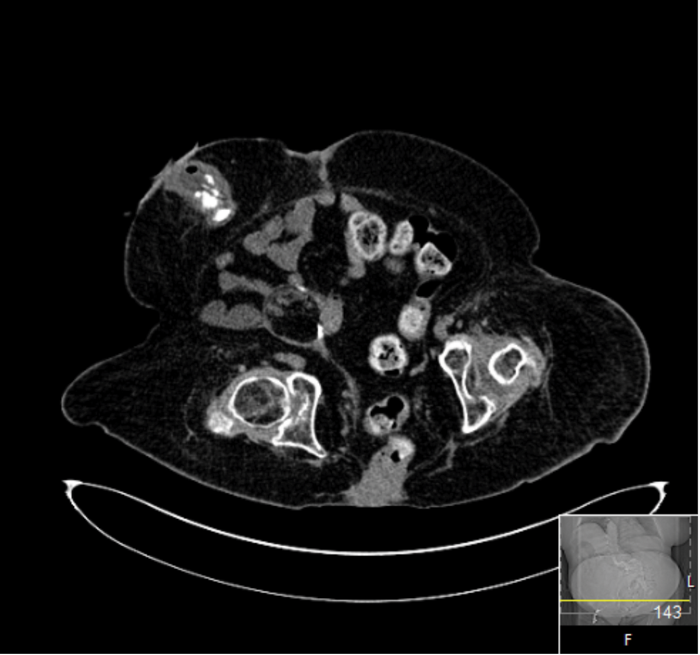

The patient was lost to short-term follow-up but a three-year CT scan demonstrated her urinary tract to be stone free (Figure 3).

Figure 3: CT scan three years’ postoperative.